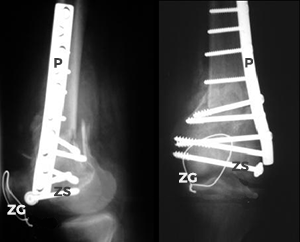

Die anatomische Rekonstruktion mittels Platte (P), Zugschrauben (ZS) und Zuggurtungsdraht (ZG) ist aufwändig aber unbedingt nötig, da sonst ein frühzeitiger Gelenkverschleiß [posttraumatische Arthrose] resultiert.